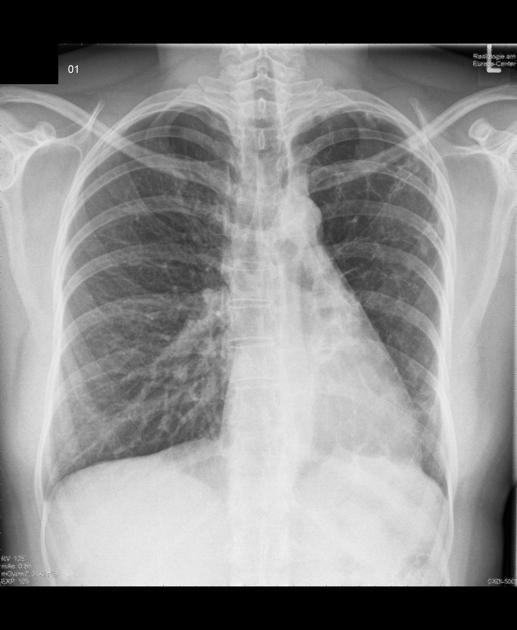

Scimitar syndrome is

Hypoplastic right lung and anomalous right pulmonary venous connection to IVC. AKA hypogenetic lung syndrome or congenital pulmonary venolobar syndrome.

Often anomalous systemic arterial supply to the right lung.